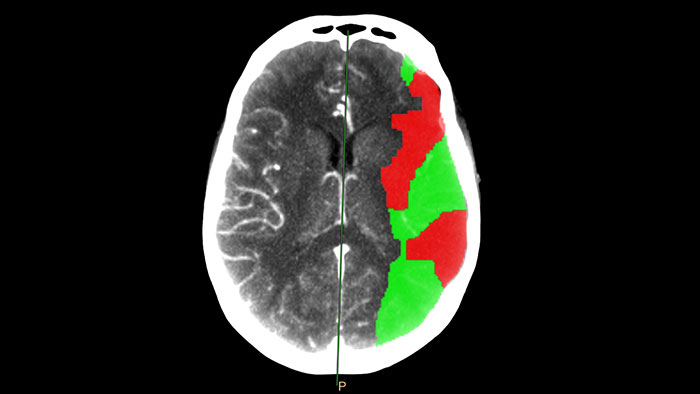

CT Brain Perfusion

Determine areas of reduced cerebral blood flow as compared to the contralateral hemisphere

Generates qualitative and quantitative information about changes in image intensity over time. The application calculates and displays quantitative color maps of cerebral blood flow (CBF), cerebral blood volume (CBV), mean transit time (MTT) and time-to-peak (TTP), and provides summary maps which may help physicians in determining areas of reduced cerebral blood flow compared to the contra lateral hemisphere.

• Perfusion and summary maps can be generated automatically and sent to PACS for convenient reviewing.

• With studies of sufficient scan duration, permeability analysis can be used as an assessment of the contrast agent permeation of the blood-brain barrier.

• The default parameters and thresholds used to create the summary maps may be edited by the user according to the physician’s preference.

• Automatic motion correction that can be further refined manually if needed.

• Quality indicators (“traffic lights”) point at possible acquisition faults that may affect the results.

• Pre-defined ROI templates for systematic and reproducible quantitative regional results.